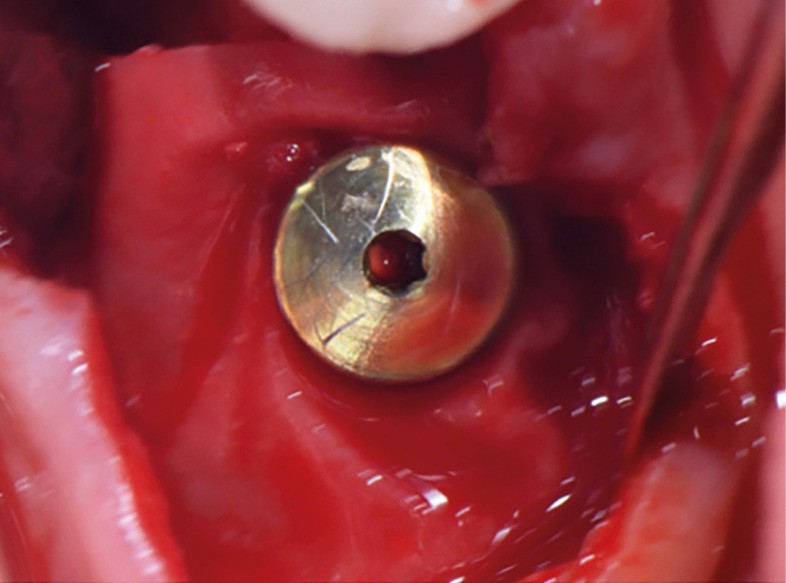

Actes préopératoires

La couronne a été déposée et une vis de couverture mise en place. La patiente a reçu un nettoyage supra-gingival général avec une attention particulière pour l’implant 47, et une irrigation locale avec du gel de chlorhexidine et du peroxyde d’hydrogène pour réduire l’inflammation des tissus. De l’amoxicilline (3 x 500 mg) a été prescrite, à commencer la veille de l’intervention chirurgicale.